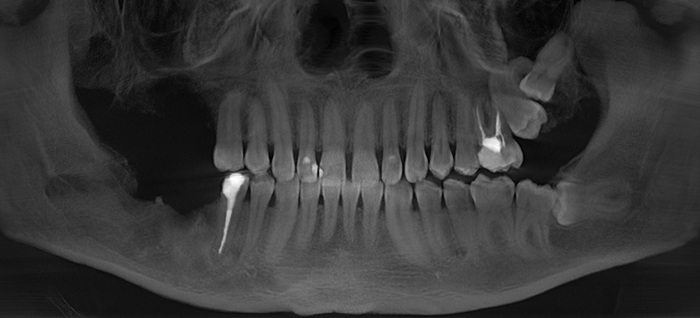

Первым контрольным рентгеновским снимком был этот:

На установленных ранее имплантатах в области 5 и 7 зубов на верхней челюсти справа (на снимке слева) стоял временный мостовидный протез. Пластик, из которого изготовляются временные конструкции не рентгеноконтрастен. Поэтому ничего кроме «белых полосок» в этой области вы не увидите. Средний срок службы подобных конструкций три месяца, но «по семейным обстоятельствам» пациент пользовался ими дольше обычного. Это привело к тому, что мостовидный протез треснул, аки старый трухлявый деревенский мост. В связи с этим, собственно, пациент и явился на прием. Напомню название статьи – «бруксизм». Сложно не заметить отсутствие зубов на противоположной стороне челюстей. Отсюда можно сделать логичный вывод, что основное (если не единственное) пережевывание пищи осуществлялось на стороне, где установлены имплантаты.